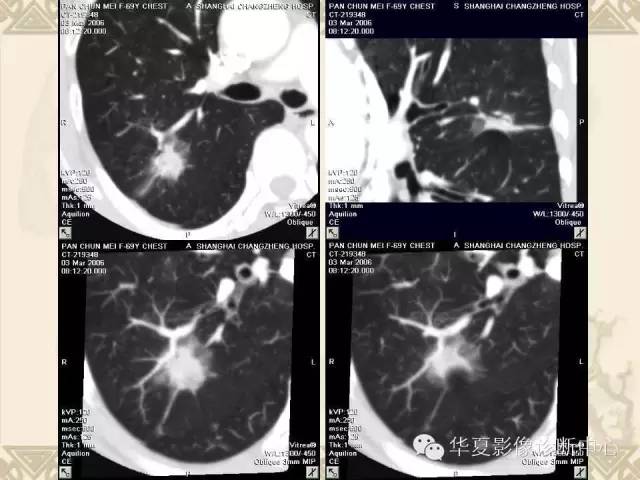

肺内磨玻璃样结节的影像诊断与处理对策